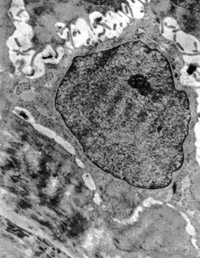

5-2-2 傷后第1天,毛細血管內(nèi)皮細胞核固縮,管腔內(nèi)血液凝集和瘀滯  TEM×6000